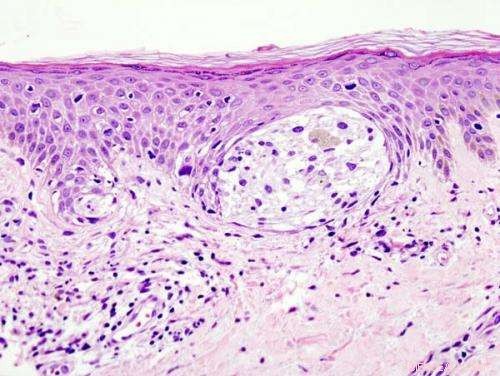

Melanoma in skin biopsy with H&E stain — this case may represent superficial spreading melanoma. Credit: Wikipedia/CC BY-SA 3.0